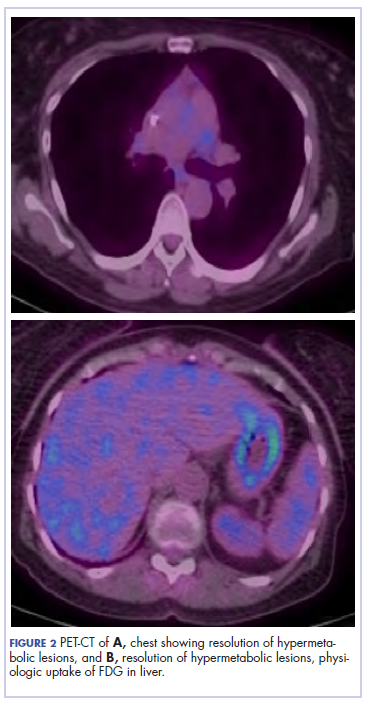

The patient underwent a CT-guided core biopsy of the spiculated nodule, which was found to be consistent with adenocarcinoma of the lung. It was negative for EGFR mutation or ALK rearrangement. She received stereotactic radiosurgery to the left posterior parietal lesion, and after completion of radiation, was started on systemic chemotherapy with cisplatin plus pemetrexed for adenocarcinoma of the lung. She received 4 cycles of chemotherapy. Repeat imaging with a PET-CT showed interval increase of the mediastinal hypermetabolic lymphadenopathy with new hypermetabolic pretracheal lymph nodes and interval development of multiple liver metastases in the right and left lobes of the liver (Figure 1). She was started on second-line therapy with nivolumab at a dose of 240 mg every 2 weeks. The treatment was complicated initially by new onset grade 2 papular pruritic rash after cycle 2 of therapy. The rash involved the upper and lower extremities, sparing the palms, soles, trunk, abdomen, and the back. It resolved with treatment delay and topical steroids.